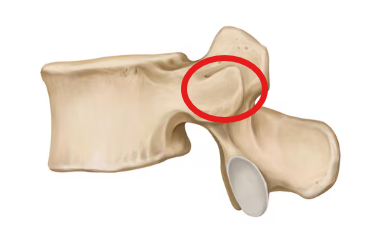

Lumbar vertebra

Superior articular process

Transverse process

Inferior articular facet

Superior articular facet

Lamina

Pedicle

Vertebral foramen